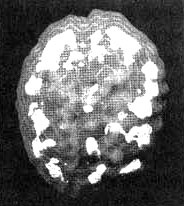

Мозг Сары — маниакально-депрессивный синдром

Иллюстрация к книге — Измените свой мозг - изменится и жизнь! [i_033.jpg]

Трехмерное изображение активного мозга — вид сверху. Обратите внимание на участки повышенной активности, разбросанные по всей поверхности коры.